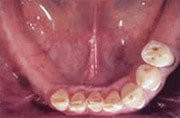

Heute

Ersatz der Unterkiefer-Seitenzähne beidseits mit natürlich aussehenden, festsitzenden Brücken und Kronen auf Implantaten.

Festsitzende Brücken und Kronen aufgesetzt